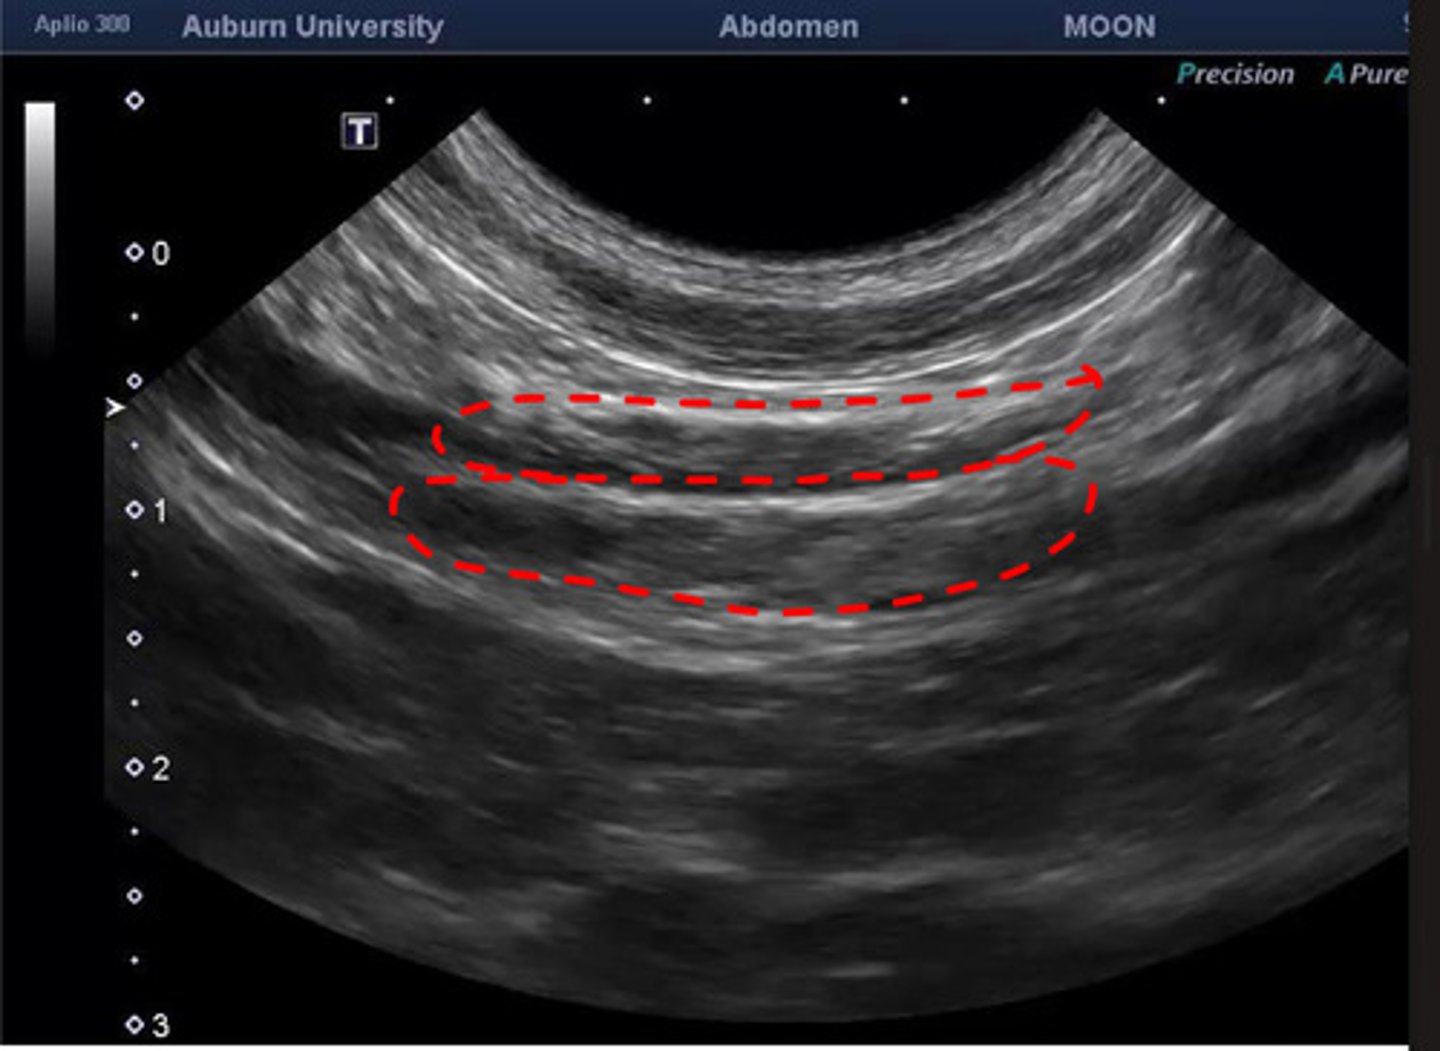

jejunal lns.

what are these lns.?

paired

the jejunal lns. are paired or unpaired?

cranial mesenteric

the jejunal lns. are 2 elongated structures on either side of the ____________ artery

jejunum, ileum and pancreas

what do the jejunal lymph nodes drain?